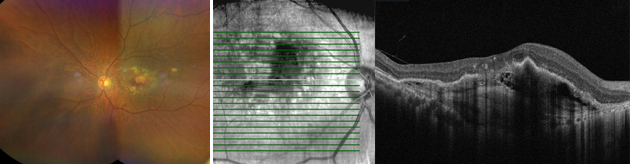

망막하출혈, 망막하액이 동반된 황반변성

치료 전